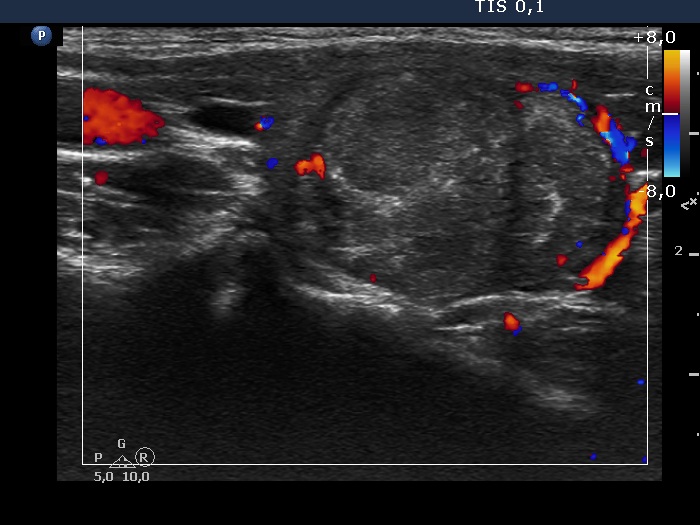

Right lobe, longitudinal scan

Right lobe, longitudinal scan, enlargement, color Doppler mode. The lesion has perinodular vascularity.